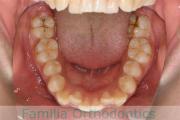

上顎

下顎

前歯の関係など

歯並びを治したいということで小学生のときに来院されました。二期治療で小臼歯抜歯の可能性が高いと判断しましたが、スペースの不足が著しいため、上下を拡大してから成長観察に移行しました。

左下犬歯に異常があったので、この歯と左右上&右下の小臼歯を抜歯してマルチブラケットを行いました。約4年、30回以上の通院が必要でした。